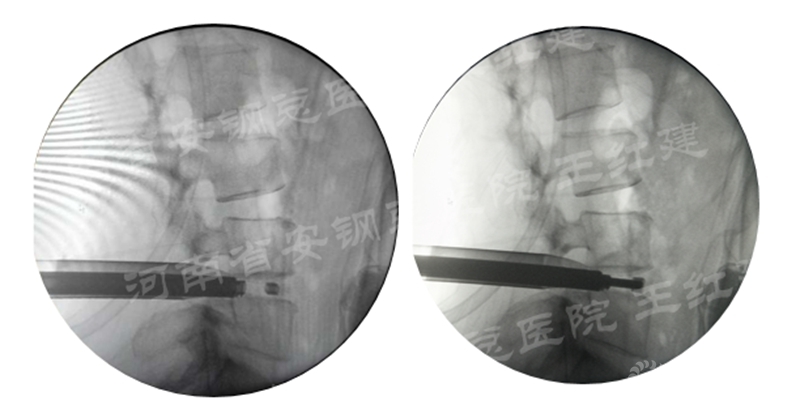

三、通道技术进行植骨、融合

应用通道技术进行植入融合时,首先要更换工作套管,通过枪钳、抓钳的应用处理椎间盘,接着进行自体骨或同种异体骨及cage植入,并通过C臂透视确定试模型号放置融合器,最终完成植骨融合。

确定融合器位置